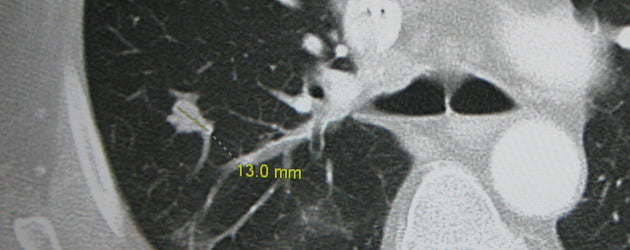

Metastasen ontstaan als kwaadaardige cellen van de oorspronkelijke tumor zich afscheiden en zich nestelen in een ander deel van het lichaam, zoals de hersenen, de longen (zie foto) of de lever. Het zijn vaak juist deze (secundaire) tumoren die uiteindelijk dodelijk zijn.